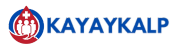

Joint Replacement

The Road to Renewal: Exploring Joint Replacement surgery As the

Arthiritis

Understanding Arthritis: A Comprehensive Guide to Symptoms, Types, and Management